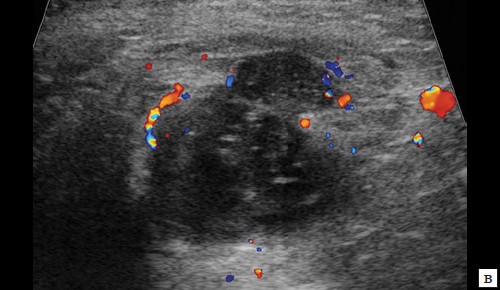

в – режим ЦДК. В подкожно-жировой клетчатке по периферии образования отмечается обогащение сосудистого рисунка;

в – режим ЦДК. Через 3 дня после оперативного вмешательства. В подкожно-жировой клетчатке по периферии гипоэхогенного образования отмечается уменьшение степени выраженности сосудистой реакции;

в – режим ЦДК. Через 14 дней после оперативного вмешательства. Сосудистая реакция в подкожно-жировой клетчатке не определяется;

б – режим ЦДК. Через 3 месяца после оперативного вмешательства. Сосудистый рисунок в подкожно-жировой клетчатке в данной проекции не обогащен.